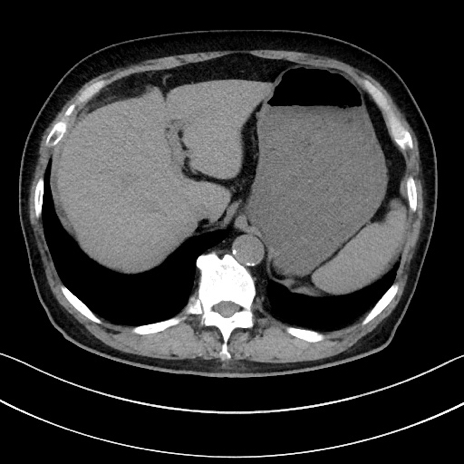

症例15(横断像)

【症例】70歳代男性

【主訴】腹痛

【現病歴】今朝から腹痛あり。全体的に痛い。特に左上の方。排ガスが今日はない。冷や汗が出る。

【既往歴】直腸癌術後

【身体所見】左側腹部〜上腹部に圧痛あり。腹膜刺激症状明らかなではない。軽度反跳痛。左下腹部に術後瘢痕あり。

【データ】WBC 7700、CRP 0.02